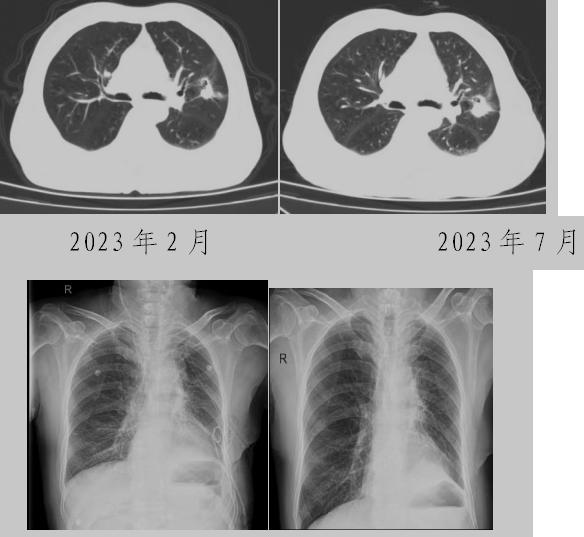

病例一:70多歲的患者王先生于2020年“急性心梗”入院時檢查發(fā)現(xiàn)了肺部結節(jié),王先生沒有在意,其間未規(guī)范復查胸部影像學檢查,于2023年2月份再次發(fā)作心絞痛時,發(fā)現(xiàn)肺結節(jié)已發(fā)展成直徑約2.5cm實性腫塊,患者在家長期口服“替格瑞洛及腸溶阿司匹林”等抗凝藥物,生活可自理,于冠狀動脈二次植入支架后三個月,收住市二院胸外科,經心內科、麻醉科等多學科會診后,由胸外科主任王松陽、副主任醫(yī)師薛飛及科室團隊行“單孔胸腔鏡下左上肺癌根治術”,術后結合快速康復理念,三天后拔除胸管,一周出院。